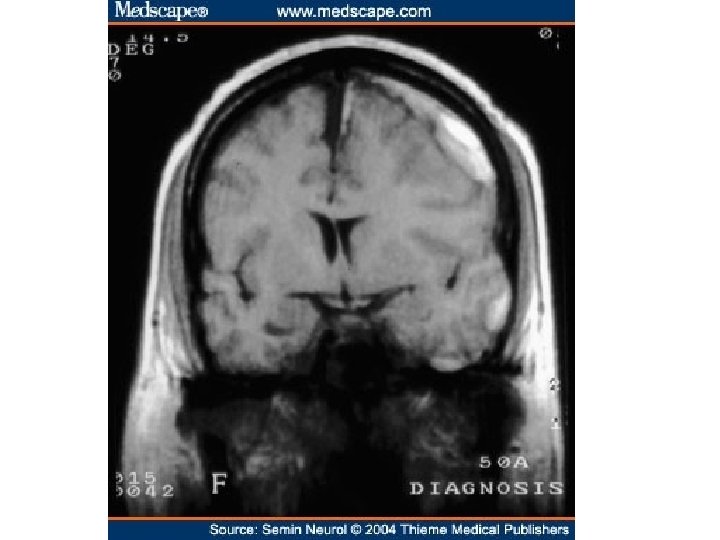

• • EDEMA SUBCUTANEOUS (“PITTING”) “DEPENDENT” ANASARCA LEFT vs RIGHT HEART PERIORBITAL PULMONARY CEREBRAL (closed cavity, no expansion) – HERNIATION of cerebellar tonsils – HERNIATION of hippocampal uncus over tentorium – HERNIATION, subfalcine